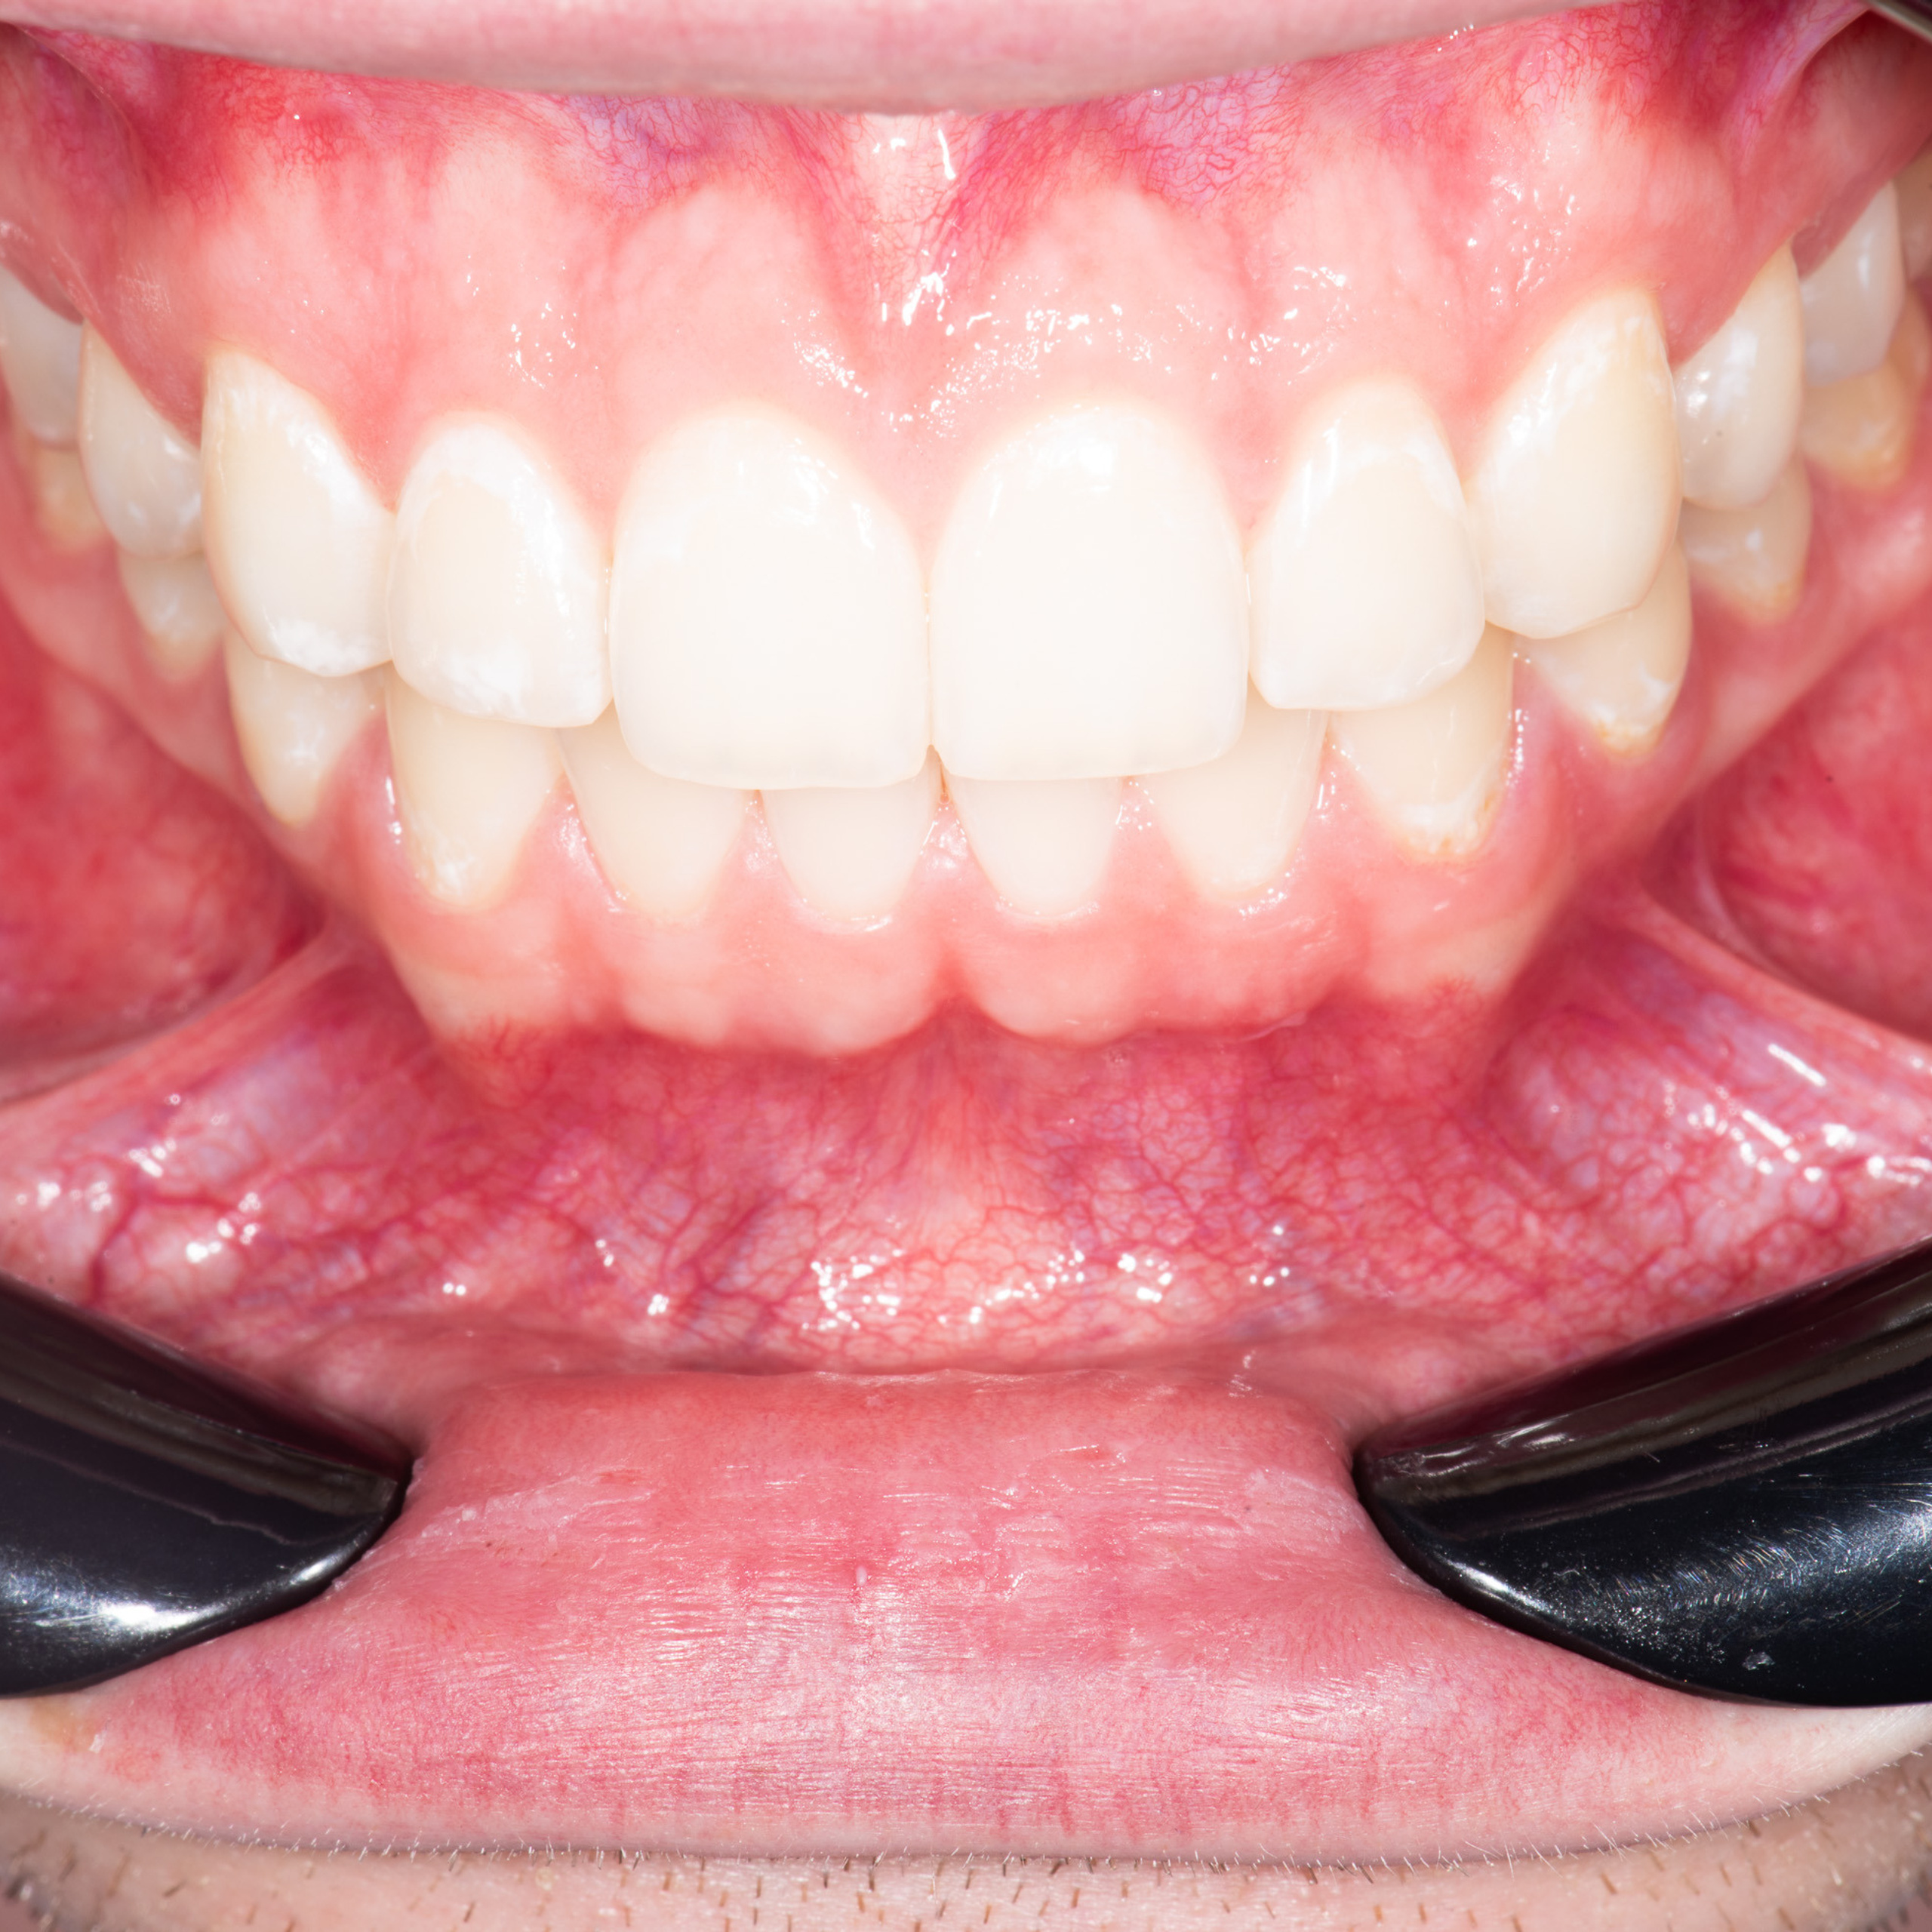

Фотографии после обучения